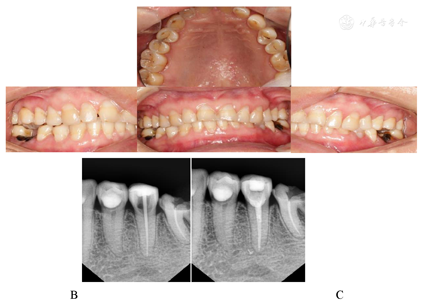

11、21、22、23、33、34去净龋坏组织达牙本质深层,质硬,敏感,光固化氢氧化钙间接盖髓,声波后牙大块充填树脂(SonicFill)充填,调

,低速精细抛光。2 d后复诊,12、32去净龋坏组织达牙本质深层,质硬,敏感,光固化氢氧化钙间接盖髓,声波后牙大块充填树脂(SonicFill)充填;13、31、41、42去净龋坏组织达牙本质浅层,直接声波后牙大块充填树脂(SonicFill)充填。自初诊1周后复诊,14、15间接盖髓后声波后牙大块充填树脂充填;43、44、45、24、25去净龋坏组织盖髓后,声波后牙大块充填树脂充填。2周后35颊侧颈部龋坏未去净露髓,在约0.7 ml阿替卡因肾上腺素注射液单颗牙局部麻醉,橡皮障隔湿下去净龋坏组织,开髓,拔髓,清理制备根管至F2X 18 mm,定位片示预备至根尖,3%次氯酸钠、生理盐水冲洗根管,拭干,氧化锌暂封。第3周复诊,35橡皮障下去除暂封物及封药,显微镜下超声荡洗根管,热牙胶垂直加压充填根管,玻璃离子垫底,声波后牙大块充填树脂(SonicFill)充填,调

,低速精细抛光。

术后6个月、1年、2年后检查充填物完好,患者自觉满意。